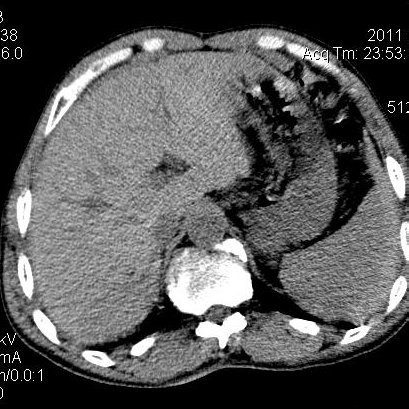

肝左叶发育异常

男性,55岁,骑摩托车摔倒后入院,自述右上腹疼痛

[backcolor=#FF0000]第一次诊断的时候也是这么肯定,可是床旁超声检查并没有发现明显异常,而且患者的一般症状都良好。还好临床只是保守治疗,没有立即手术,第二次复查的时候没有一点变化,又做了MRI检查,没有血肿,

这是一例肝左叶发育异常的,很个性吧~[/backcolor]